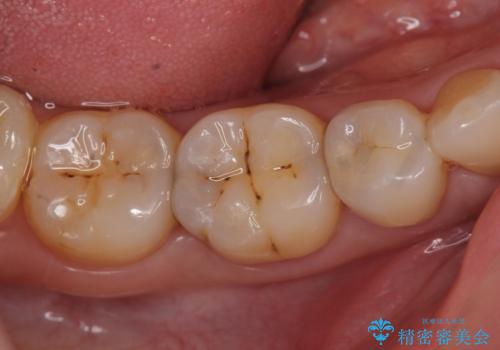

- 右下の奥歯がしみるので診て欲しいといらっしゃった方の症例です。

右下5は虫歯が大きかったため、虫歯を除去後、オールセラミッククラウンによる補綴を行いました。

右下6、7は虫歯を除去後、セラミックインレーによる修復を行いました。